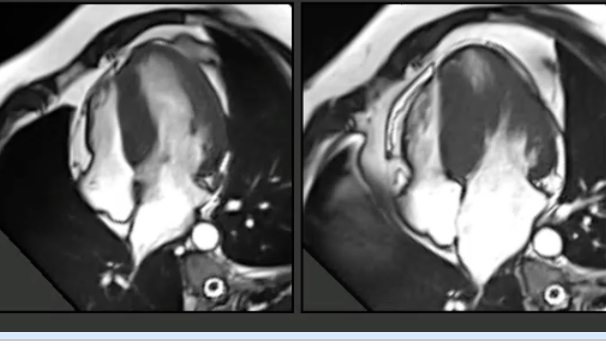

CMR in NSTEMI

This post is for subscribers only